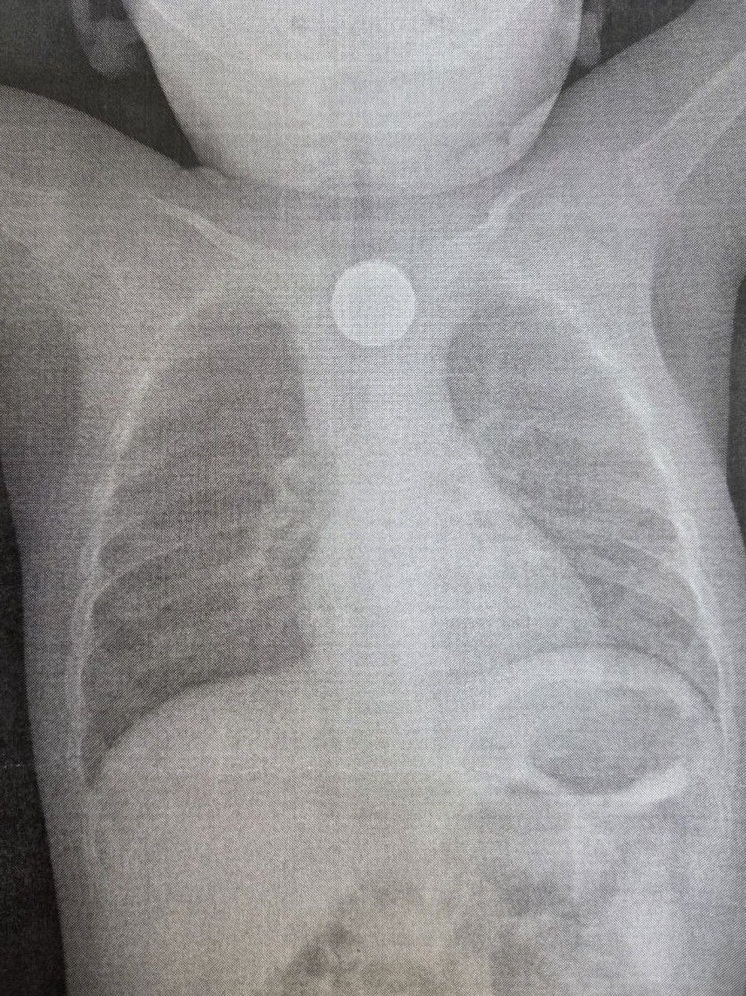

Срочная операция была проведена в Детской республиканской клинической больнице (ДРКБ) в Улан-Удэ, где медики спасли жизнь годовалому пациенту. Малыш проглотил дисковую литиевую батарейку и двухрублевую монету, что привело к тяжелейшему химическому ожогу пищевода.

Поводом для обращения за медицинской помощью стало резкое ухудшение состояния ребенка 27 ноября. У малыша началась многократная рвота, а спустя два часа поднялась температура и появились хрипы при дыхании. После осмотра в центральной районной больнице, где было диагностировано инородное тело в пищеводе, ребенка экстренно направили в ДРКБ, рассказали в учреждении здравоохранения.

Специалисты больницы оперативно провели эндоскопическое вмешательство. Бригада в составе врача-эндоскописта Зорика Хангалова, медсестры-эндоскописта Ларисы Никитиной и анестезиолога-реаниматолога Романа Цвикевича извлекла опасные предметы. Находясь в пищеводе, литиевая батарейка вызвала химический ожог слизистой оболочки третьей степени, создавший прямую угрозу жизни ребенка, подчеркнули в ДРКБ.